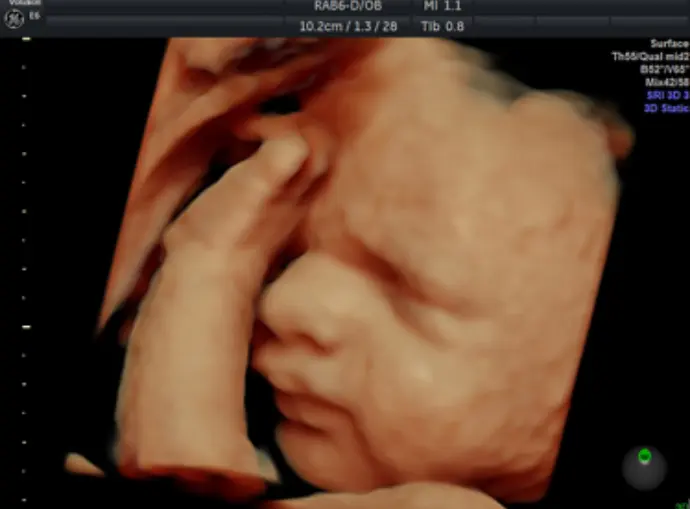

Gallery: 4D Scan Images & Videos

All of the baby scans we perform here at First Encounters are carried out using top-quality ultrasound equipment. For 3D/4D scans, we use the GE Voluson E6, featuring genuine HDLive technology. GE Healthcare are the world’s leading providers of pregnancy scanning equipment, and HD Live scans give an unparalleled level of detail and clarity.

Scroll down to view some examples of the 4D scan images and videos our sonographers are able to capture.

4D Scan Images

During your 3D/4D scan, we’ll capture multiple photographs of your unborn baby, giving you and your family a set of stunning keepsakes that you’ll treasure forever. All of your scan images will be available to download from photocloud™, plus we can provide glossy souvenir photos for you to take home.